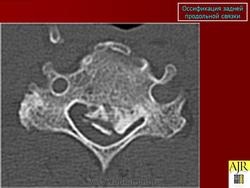

КСС. Оссификации. +

Оссификации.